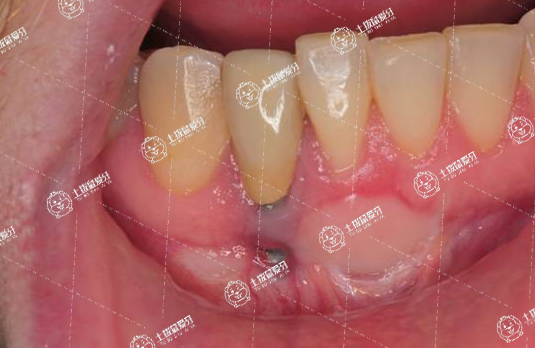

牙齒矯正期間有黑三角需要待正畸治療結束后,選擇修復治療或膜齦手術治療。

正畸治療過程中可能因為牙齦退縮或牙齒移動出現(xiàn)黑三角,這種情況可能是暫時的,也可能是永久的,所以消除黑三角的治療,需要待正畸結束后再進行。

可以選擇制作貼面或全冠修復體,修改牙齒外觀形態(tài),以消除黑三角,也可能進行膜齦手術,通過移植結締組織,使牙齦重新覆蓋牙頸部,消除黑三角。

若黑三角癥狀不見緩解,或伴有其他癥狀時,應及時前往醫(yī)院就診,明確原因后給予針對性治療。